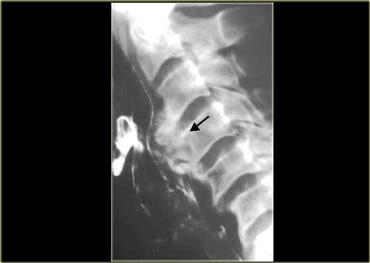

Gai xương (mũi tên) có thể chèn ép vào thực quản và hạ họng.

Tuy nhiên, chúng hiếm khi gây ra triệu chứng lâm sàng.